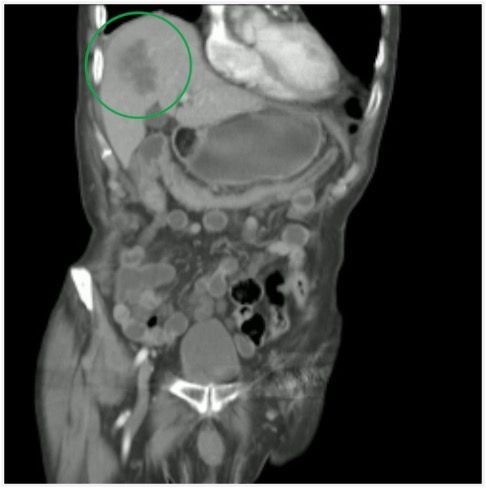

A middle-aged man presents with abdominal and right flank pain. What is the diagnosis?